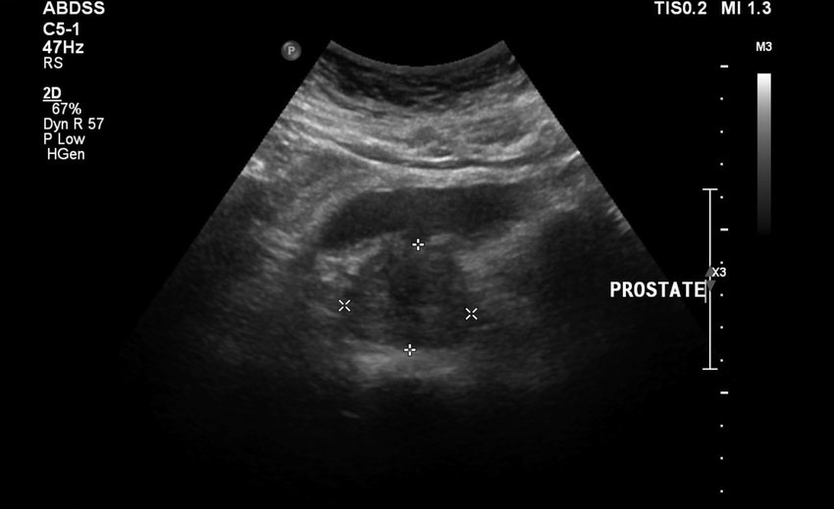

Non hanno lasciato che i gommati vivono con calma, quindi è stato aggiunto il mal di schiena, i test e i risultati dell'ecografia erano cattivi. Era letteralmente impossibile allontanarsi dal bagno, c'era una sensazione di pesantezza all'inguine e al dolore costante. È stato prescritto il massaggio diretto della prostata, che mi ha immerso nel panico. Ha iniziato a cercare altri metodi di cura meno traumatici.